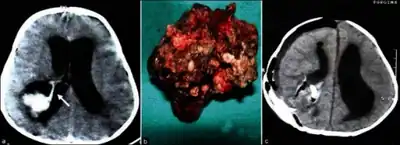

- Micrograph of a choroid plexus papilloma. H&E stain.

- Plexuspapillom Detail

- Plexuspapillom Overview

Diagnosis

In terms of the diagnosis for Choroid plexus papilloma we find the following:[3]

- MRI

- Neuropathology (tumor tissue)